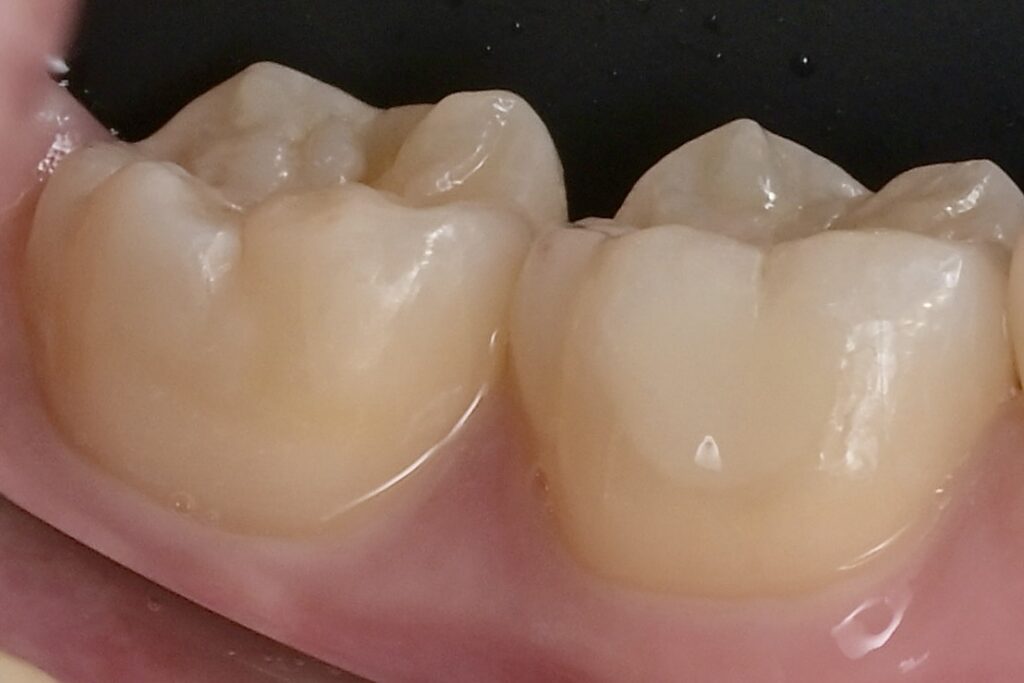

審美歯科・セラミック治療

50代 虫歯治療 セラミック治療 e.maxテーブルトップ

07審美歯科

審美歯科では素材や手法を変えながら、審美的なアプローチを提案しています。見た目にコンプレックスがあると、自信を持ちづらくなることでしょう。そういった患者様一人ひとりの、口もとの印象を改善し人生が豊かになるようにしたいと考えています。審美治療を通し、その手助けをさせてください。